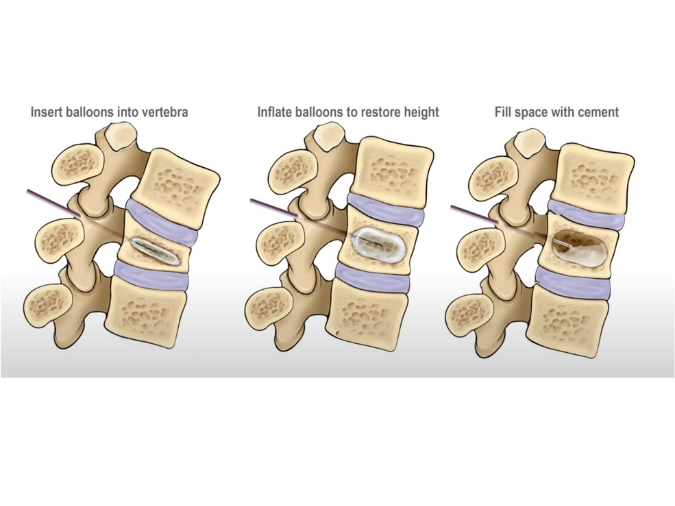

– Kyphoplasty involves the use of a balloon-like device to create a cavity within the fractured vertebra before injecting the bone cement.

– The balloon is inflated to restore the height of the collapsed vertebra and create space for the cement.

– Once the cavity is created, the bone cement is injected, stabilizing the fracture and reducing spinal deformity.

- Procedure: The procedure is performed by an interventional radiologist or spine surgeon. Using fluoroscopic guidance, a small incision is made in the skin, and a needle is advanced into the fractured vertebra. In vertebroplasty, bone cement is injected directly into the vertebra. In kyphoplasty, the balloon is inserted and inflated to create a cavity before injecting the cement.

– Restored vertebral height: Kyphoplasty, in particular, can help restore the height of collapsed vertebrae, reducing spinal deformity and improving posture.